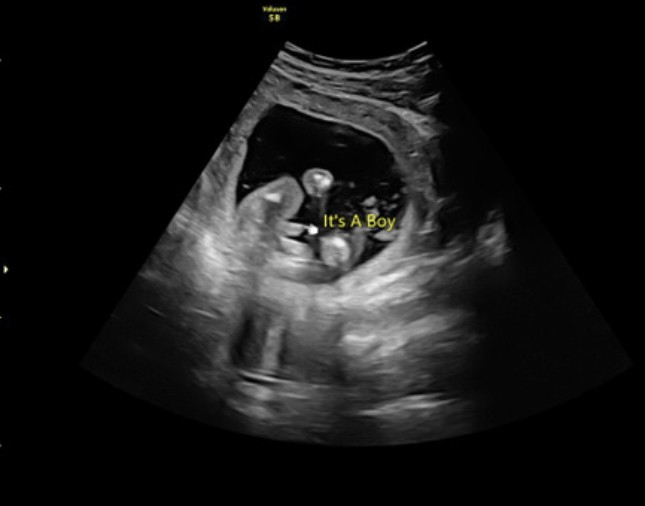

Czy na tym zdjęcie napewno chłopiec?

Załączniki

• F4957AB9-5A2B-4F1D-8A2B-19C90CF106F8.jpeg

F4957AB9-5A2B-4F1D-8A2B-19C90CF106F8.jpeg

27,4 KB · Wyświetleń: 252